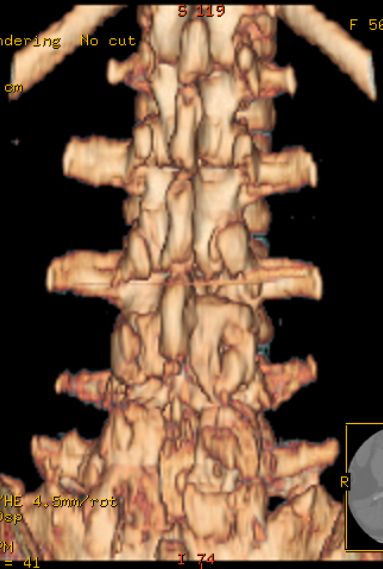

以下是引用余辉在2007-9-4 21:00:00的发言:[br]椎体棘突有点异常(像是被切割了),不知有否手术史,如椎体融合术等。单纯的退行性变可以出现椎间隙变窄,但同时一般会出现椎体上下缘的硬化增生,且椎体间完全融合的机率更小,本例椎体完全融合且椎体上下皮质缘破坏掉了,如果没有手术史,就应该考虑椎间盘炎性病变了,且椎体棘突及棘间韧带的变化也并不是不支持这个,多数小关节也融合了,且其形态也容易让人联想到如强脊炎及类风关等病变。[br][br][本贴已被 余辉 于 2007-9-4 21:03:55 修改过]

以下是引用chry3在2007-9-4 20:42:00的发言:[br]椎间盘病史?是什么样的病史,无双下肢放射痛,那就不是椎间盘突出了。是感染、什么性质的?[br]从图象看椎间隙消失,椎间盘组织未见,锥体滑脱是因为椎间盘溶解造成的[br]l4、5椎体骨质结构未见异常,l5上缘是l4的长期压迫所致[br]还是考虑椎间盘感染,结核。[br]